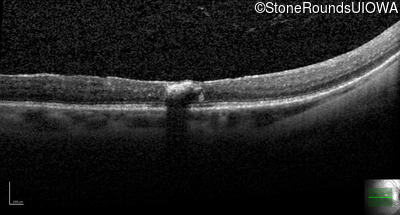

Autosomal Dominant Vitreoretinochoroidopathy (III4A)

Age at visit: 47 years

This 47 year old woman began wearing glasses at age 5 and had cataract surgery at age 32. At that time her doctor noticed a retinal abnormality.

Autosomal Dominant Vitreoretinochoroidopathy BEST1 Tyr72Asn TAC>AAC   AD